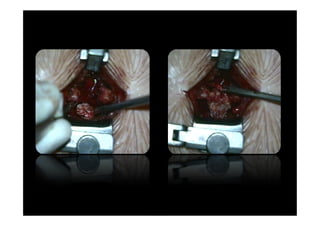

•small incision • interlaminar space

exposed

•adequate retraction •laminotomy

•small incision •interlaminar space exposed •adequate retraction •laminotomy